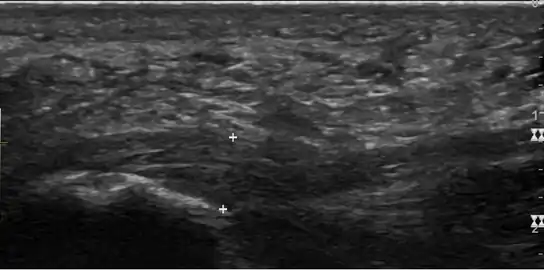

a)Ultrasonographic finding of plantar fasciitis b)normal sonographic finding

Thickened plantar fascia in ultrasound

Imaging

Medical imaging is not routinely needed. It is expensive and does not typically change how plantar fasciitis is managed.[15] When the diagnosis is not clinically apparent, lateral view X-rays of the ankle are the recommended imaging modality to assess for other causes of heel pain, such as stress fractures or bone spur development.[7]

The plantar fascia has three fascicles-the central fascicle being the thickest at 4 mm, the lateral fascicle at 2 mm, and the medial less than a millimeter thick.[18] In theory, plantar fasciitis becomes more likely as the plantar fascia's thickness at the calcaneal insertion increases. A thickness of more than 4.5 mm ultrasound and 4 mm on MRI are useful for diagnosis.[19] Other imaging findings, such as thickening of the plantar aponeurosis, are nonspecific and have limited usefulness in diagnosing plantar fasciitis.[13]